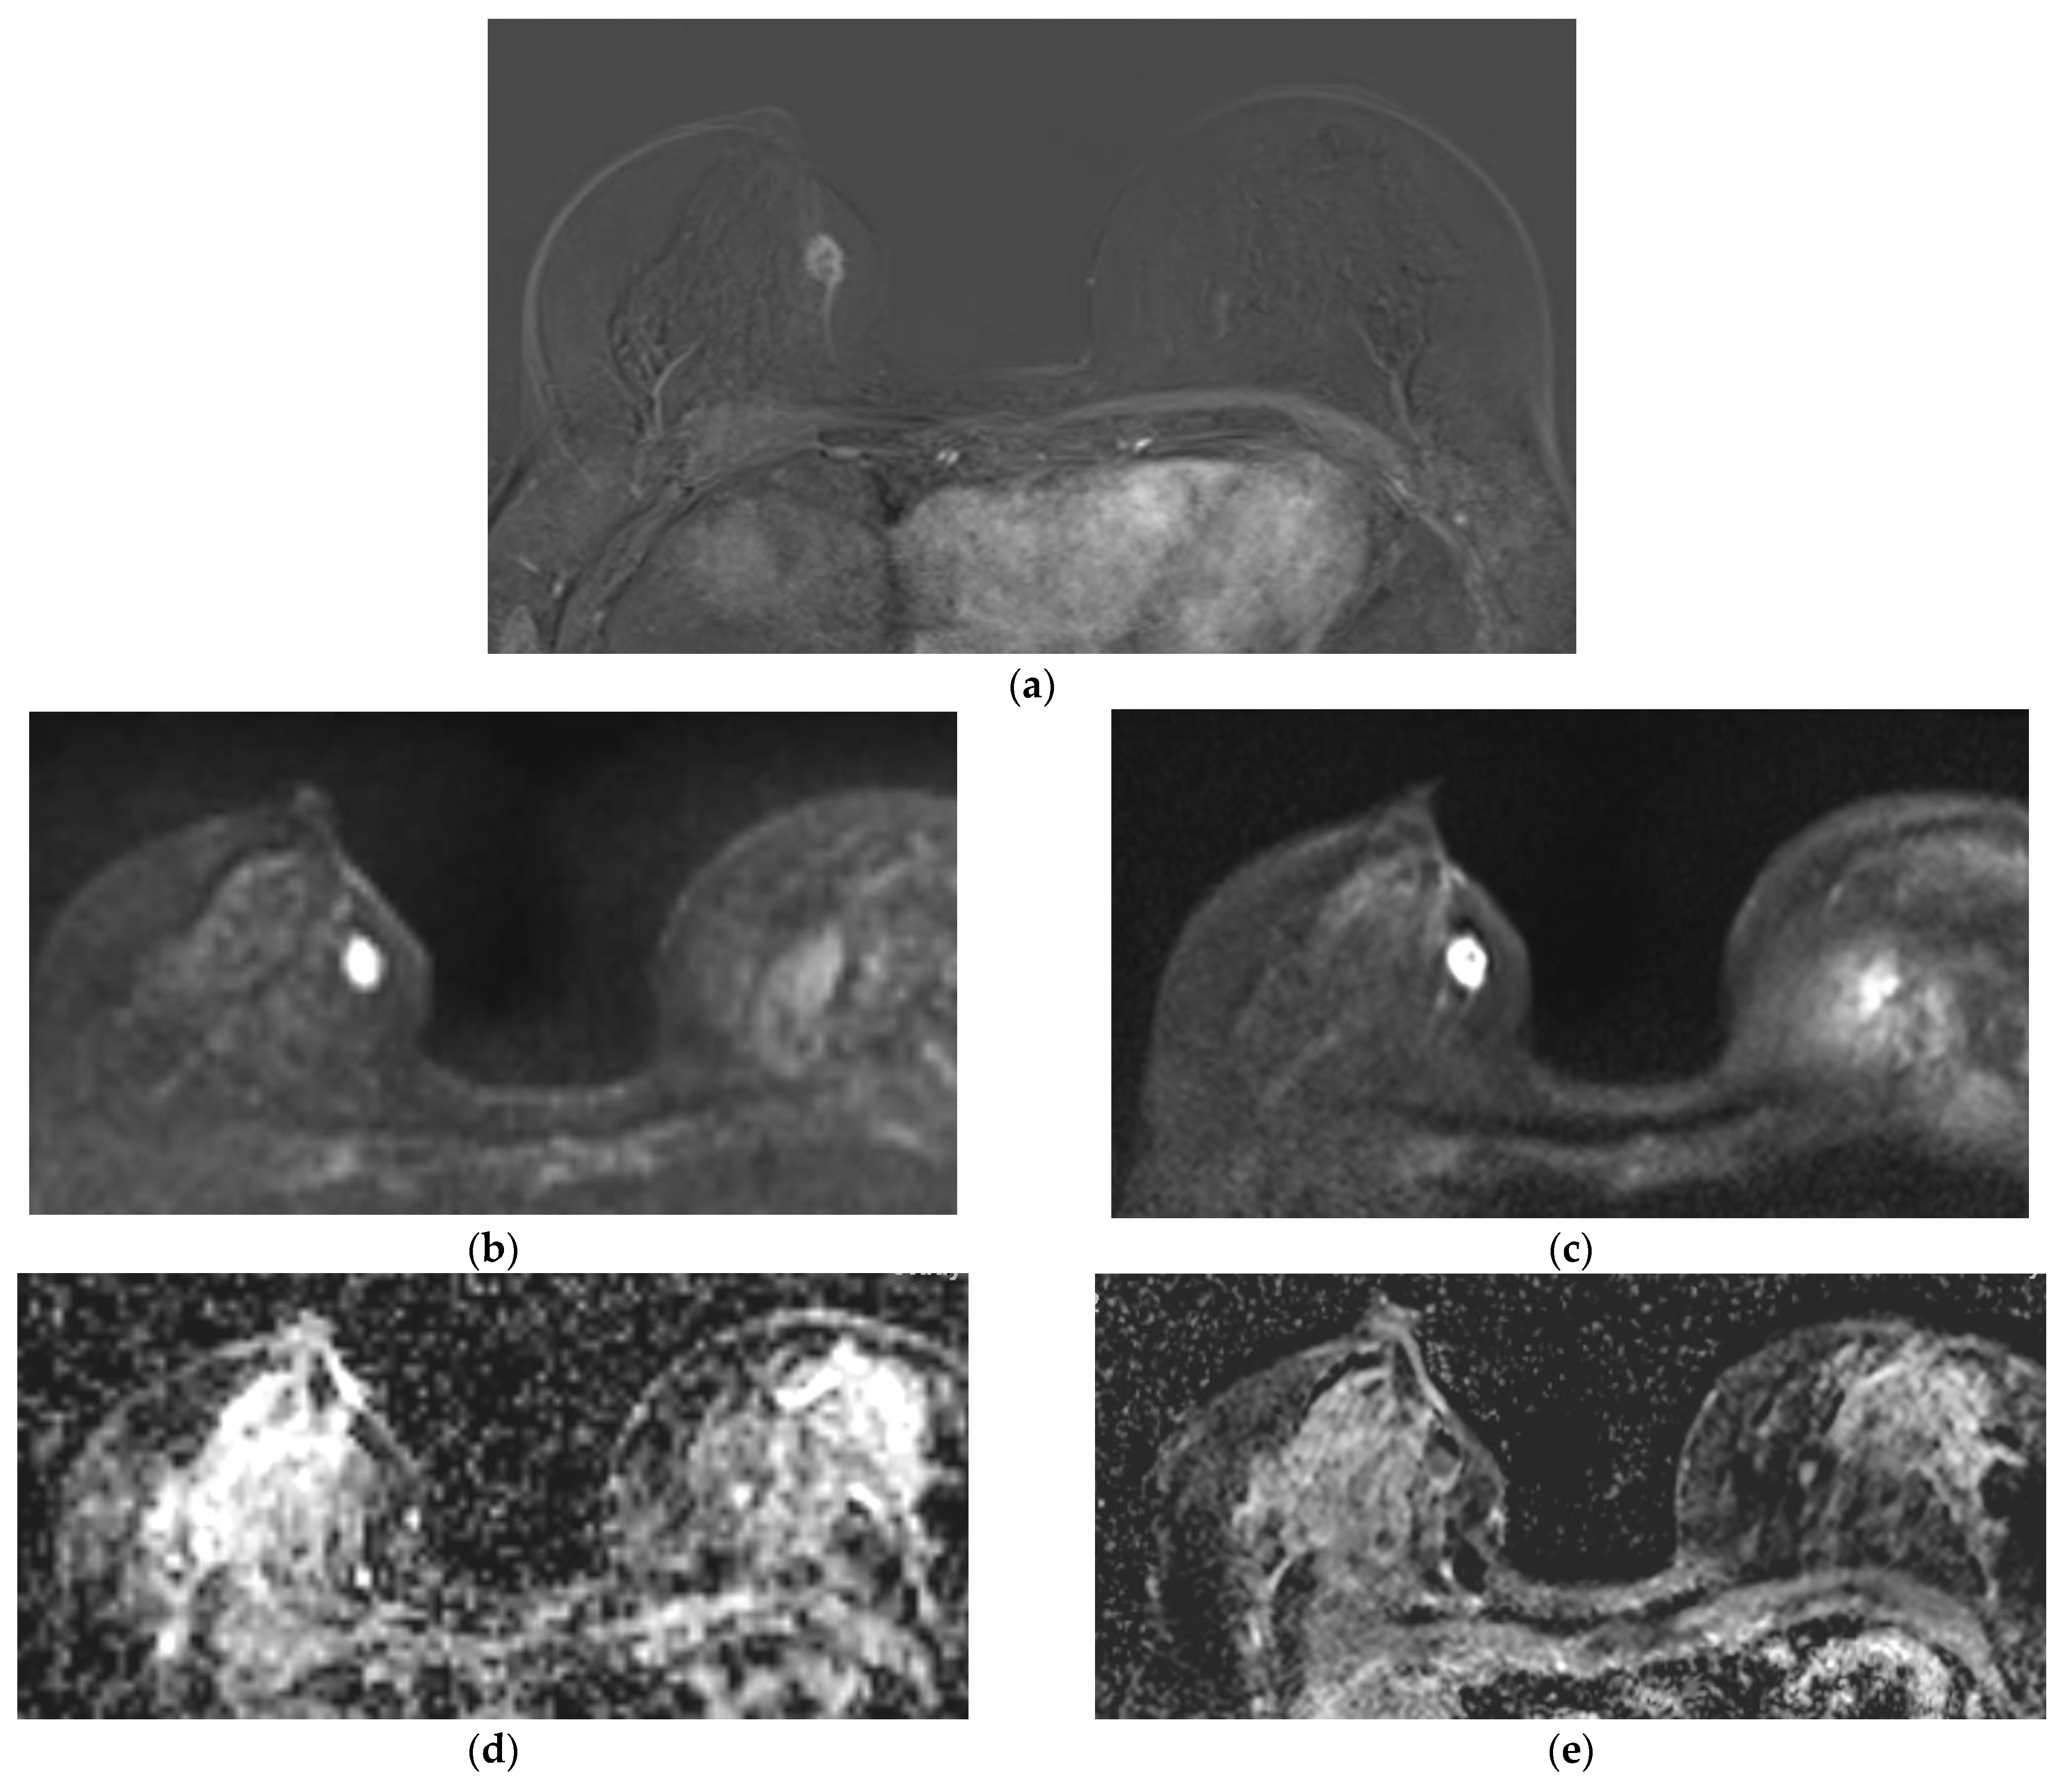

Qualitative Image Evaluation for DWI

Qualitative Image Evaluation for ADC